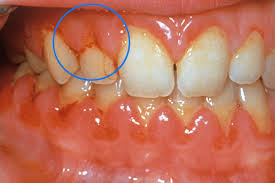

- 치은염(잇몸염증): 치석, 치태로 인한 세균 감염

- 잇몸 출혈이 반복되거나 잇몸이 움푹 패이기 시작할 때